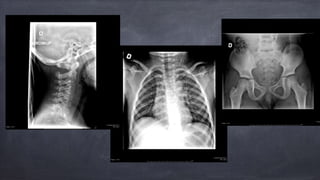

• 5.

Circonstances de l’accident fillette de 6 ans dormait dans l’auto passagère arrière d’une voiture allant à 100 km/h face à face vers 19h00

• 6.

Sur la scène Encore attachée, trois points (?) Pas de perte de conscience, pas de convulsion Plainte spontanée de douleur abdominale Pas de plaie, pas de signes de fracture Pas de cervicalgie

• 7.

Transportée P &C au centre hospitalier référant Approche ATLS Stable au niveau A-B Au niveau cardio-vasculaire: FC 120-150 TA normales-hautes 120-135/80-85

• 9.

vomissements à 5-6reprises, nausée Douleur abdominale importante, ballonnement ecchymose a/n quadrant inférieur

• 11.

Transfert demandé Équipeinquiète de la douleur abdominale FAST négatif à 2 reprises Trauma rate? Seat belt injury?